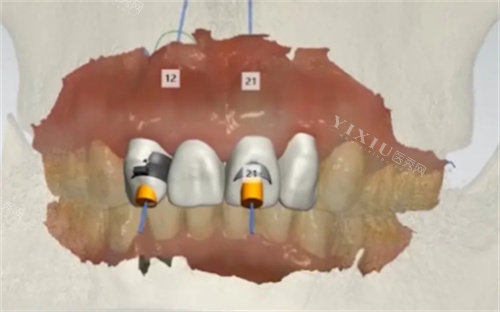

技术比较靠前:科室配备智能化口腔CT、3D打印种植导板等新型设备,实现精细诊疗。例如,种植牙手术采用小创口技术,创口小、改善快,患者术后满意度达98%。

术后护理:种植牙、矫正等治疗后,需严格遵循医嘱,定期复查。